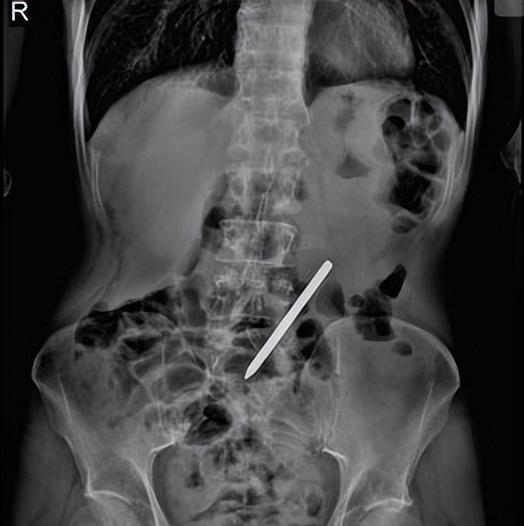

常先生的自虐行为引发了他的身体疼痛和担忧,最终他不得不去医院求助。医生检查后发现,异物位于十二指肠远端,这是消化系统中非常关键的位置。异物的存在对常先生的健康构成了严重威胁。医生决定采取行动,并使用高风险的手术来移除异物。医生使用小肠镜精确地定位异物并成功地将其取出,挽救了常先生的生命。这个案例提醒人们,不应该轻易地采取自虐行为,而应该及时寻求专业帮助并珍惜生命。近日,一段引发争议的视频在互联网上疯传。视频中,一位外籍自行车运动员在比赛结束后将自己的水壶送给了一个小男孩。然而,随着当事人的辟谣,事情变得更加复杂。这个事件背后的真相究竟是什么?我们需要了解更多的信息才能做出正确的判断。这个故事告诉我们,情感和心理对人类行为的影响是深刻的。常先生因为情感激动而采取了自虐行为,最终陷入了极大的危险。